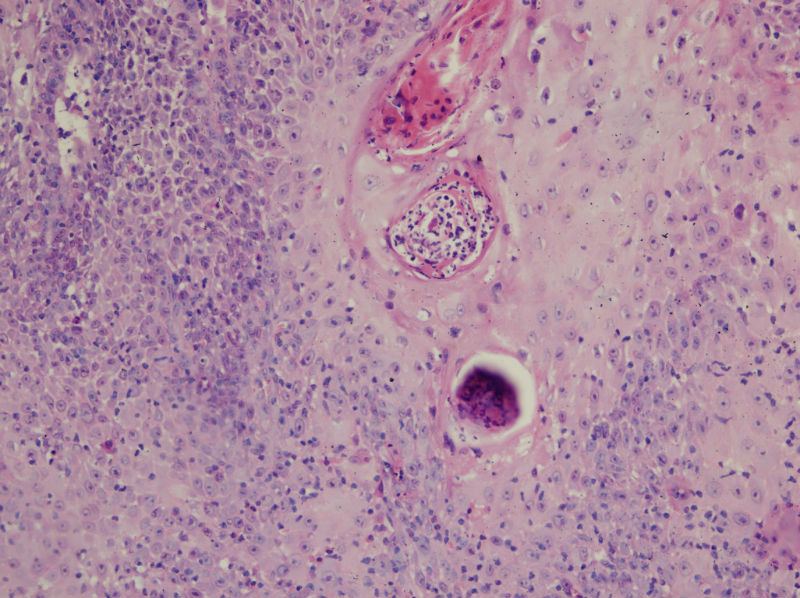

男,45岁,上唇菜花样肿物,请老师指教

图2